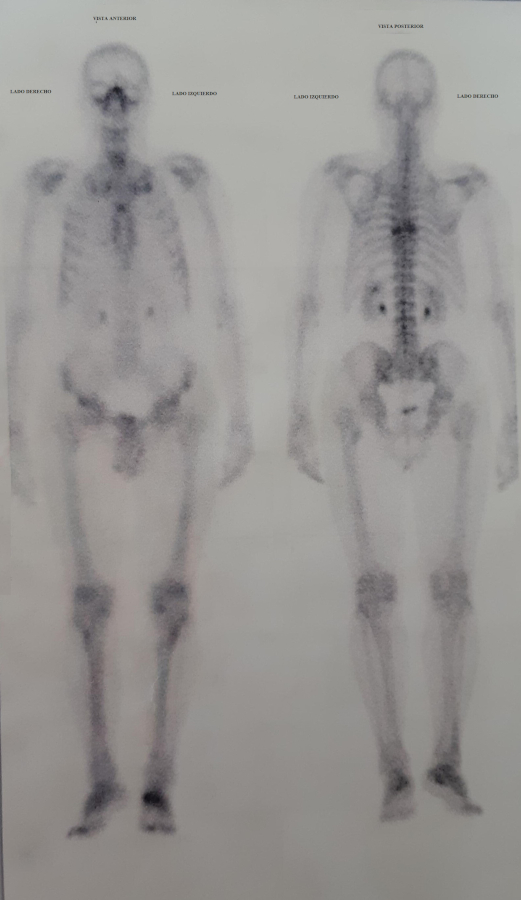

En relación a estas últimas patologías, se solicitó a la Secretaría actuante la entrega de estudios médicos antemortem. Como resultado de dicha diligencia, se pudo contar con una resonancia nuclear magnética que muestra aplastamiento vertebral por fractura patológica a nivel de la octava vértebra torácica. Además de esto, se realizó un centellograma óseo que mostró a nivel de la D8 hipercaptación del material radioactivo, a partir del cual se orientó la investigación a una identificación tentativa (Fig. 9).